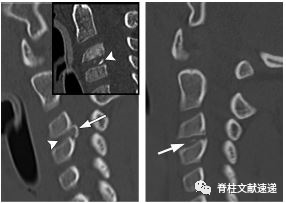

图注:49岁男性,极外侧腰椎间盘突出症。

PET成像不能作为评价椎间盘病变情况的主要方法。椎间盘突出,特别是急性或亚急性时,并伴有炎症反应,可导致PET局灶性FDG摄取。

图注:49岁男性,极外侧腰椎间盘突出症,有黑色素瘤病史。(e) 轴位PET图像显示病灶部位有FDG摄取,怀疑黑色素瘤转移。经过3周的保守治疗,病人的病情有所好转。临床上并没有黑色素瘤诊断。